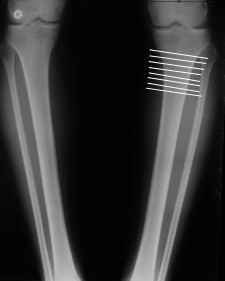

Мне представляется оптимальным на уровне 3-4 линии (т.е. как раз посредине отмеченной зоны). Если рассчимтываешь делать медиализацию, то параллельно суставной поверхности, иначе просто не сдвинешь без джистракции - отломки зацепятся. Если без медиализации - то вообще не имеет значения.

Ты же понимаешь, опыт эмпирический. Было дело - промахивался с метками - делал сантиметра на 2-3 ниже сустава - всё было хорошо.

Сложно только цеплять короткий фрагмент, особенно когда удлинение. Спускался ниже - 5-7 см ниже сустава - тоже всё хорошо. Ниже уже бессмысленно - диафиз, ломать труднее, срастается дольше.